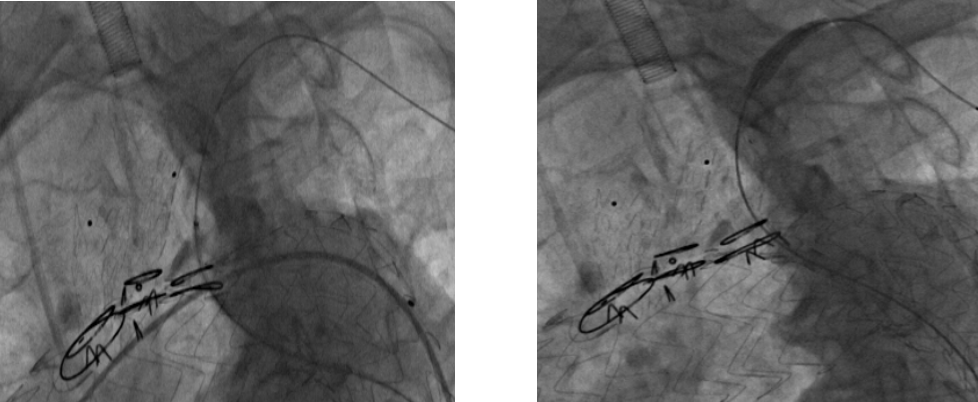

术前CTA

术前

术后

手术用时80分钟